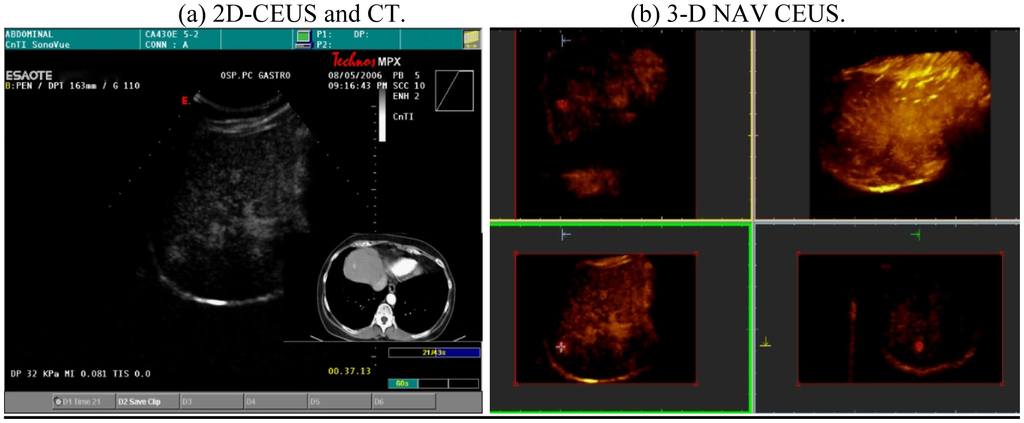

Our previous, as yet unpublished, experience [11] showed that 3-D US was a technique useful to perform detection of HCC: We demonstrated that it was possible to detect HCC using the 3-D software in the US machine (TECHNOS MPX, Esaote, Italy) with free-hand technique. The limit was that the 3-D reconstruction of the liver was dependent on the type of scanning; in other words, the acquired volume was not corrected in the three dimensional space. To obviate this problem, we used an adapted software within a commercially available machine, called NAVIGATOR (Esaote, Italy) (and recently described as real-time guidance using a fusion imaging system that combines US and CT information in the targeting and subsequent radiofrequency thermal ablation (RFTA) ablation of a liver target inconspicuous [12]), to capture a continuous scanning of the entire liver. This scanning, called NAVIGATOR 3-D CEUS, was possible both with conventional US and with contrast-enhanced US; the post-processing fusion technique consistently demonstrated that the CT and US 3-D reconstruction of the liver were exactly superimposable.

This scanning was possible both with conventional US and with contrast-enhanced US; the navigator system is furthermore able to perform a volumetric reconstruction of liver with CT scanning and to compare the two different volumes (US and CT) employing the fusion technique (Figure 3).

This superimposes each resliced layer of US and CT volumes showing both on the monitor: The post-processing fusion technique has consistently demonstrated that the CT and US 3-D reconstruction of the liver were exactly superimposable (Figure 4).

To easily perform a 3-D reconstruction of a 2-D acquisition of CEUS imaging of the whole liver, the 2-D acquisition is performed with real time scanning perpendicularly on the long-axis of the liver, for a complete 2-D image of its short-axis (Figure 2). The subsequent reconstructions of these planes show a rendered volume with a “parenchimal” aspect (Figure 5) or with a “vascular” map (Figure 6) of all the hepatic segments with an acquisition in the early arterial and in portal phase.